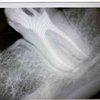

Хирургический протокол.Базовый курс по дентальной имплантации

Лектор Павленко М.Ю., Базовый курс по дентальной имплантации

Стоматология, Прогрессивная цифровая имплантология

Стоматология , Повторное эндодонтическое лечение.техника выполнения основных клинических протоколов